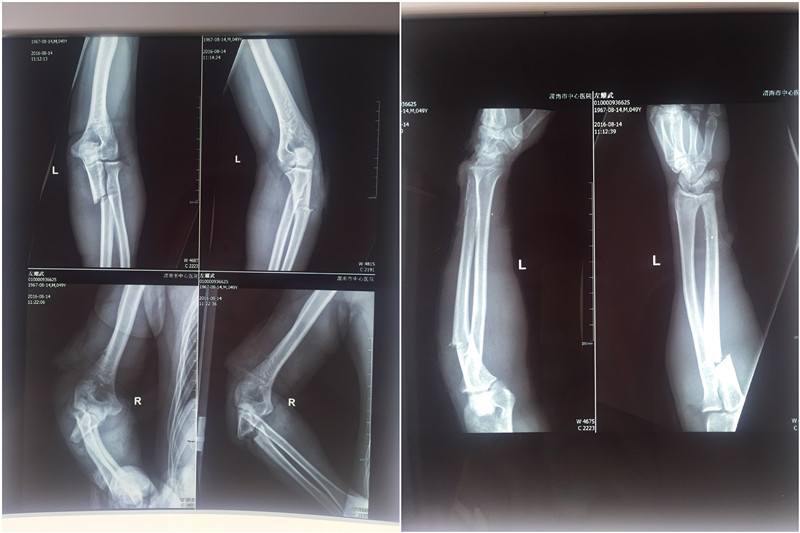

近日,一名中年男子左先生遭遇意外,被数人用刀砍伤双上肢及左下肢,立即被120送往我院急诊科,骨一科接到急诊科会诊电话后迅速对左先生进行紧急抢救。经过快速输液、拍片等检查,随即转往骨一科进一步治疗。初步诊断为:双侧尺骨多处开放性骨折、桡骨开放性骨折、右侧肱骨开放性骨折、桡神经丶尺神经、肌皮神经断裂、全身多处肌肉、肌腱断裂。

手术前